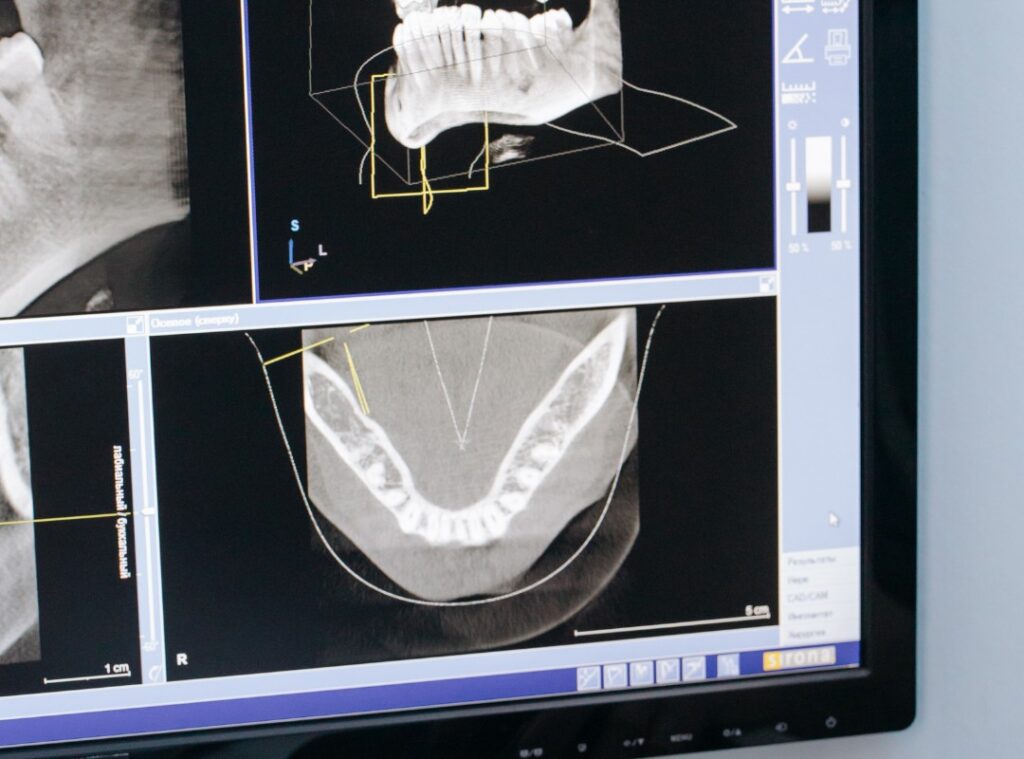

CAD/CAM dentistry utilizes advanced digital technologies for the planning, design, and production of dental treatments. Through this technology, dentists can obtain a precise 3D digital model by scanning the patient’s teeth and oral structure. Using this digital model, custom restorations such as veneers, crowns, and bridges are meticulously designed.

The CAD/CAM systems transmit these designs directly to milling machines, allowing patients to receive their custom restorations in a much shorter time frame. This method significantly contributes to the digital planning process while offering a more comfortable and efficient treatment experience for our patients.

Cephalometric X-ray

Cephalometric X-ray is a preferred medical imaging method used to evaluate the structure of the jaw and face. This X-ray is utilized by orthodontists and maxillofacial surgeons to examine and diagnose jaw relationships, facial profiles, and the overall dental and skeletal structure. A cephalometric X-ray captures a lateral (side) view of the individual’s head and face.

By providing precise measurements of various anatomical points, bone structures, and teeth, it enables an accurate diagnosis. These measurements allow for the effective planning of necessary treatments and the monitoring of treatment progress. Cephalometric X-rays play a crucial role in understanding patients’ oral and jaw health and determining the most appropriate treatment options.